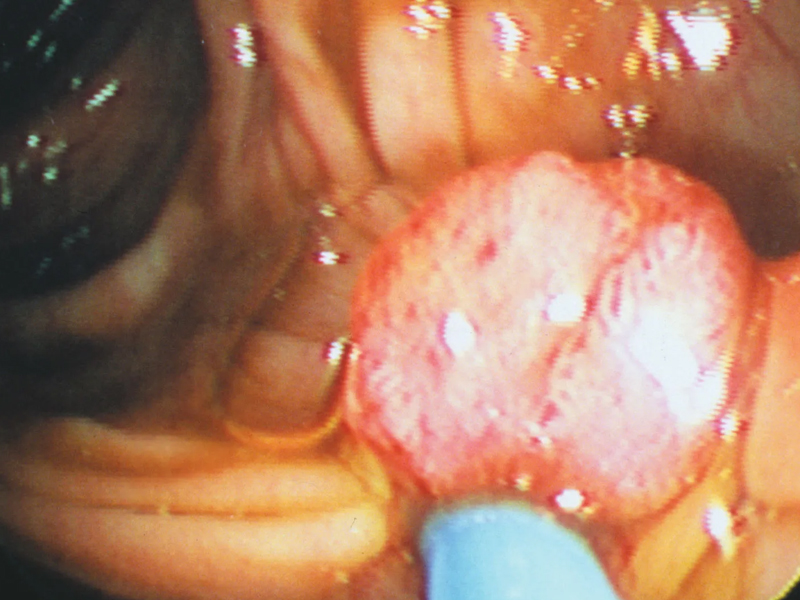

| 腸道長了息肉,上廁所會有 3 個警告,別等到晚期了才發現 身體出現了任何看似很小的問題,都可能是一個嚴重的疾病的前兆。那麼關於腸息肉,都會有哪些身體上的提醒或警告呢? 腸息肉:腸道中的「小肉芽」 腸息肉是一種常見的腸道疾病,它是一種良性的腸道腫瘤。 通常情況下,腸息肉並不會造成太大的影響,但是如果不及時治療,它可能會發展成為惡性腫瘤,給人體健康帶來威脅。 腸息肉的發生主要是由於腸壁黏膜增生形成的,隨着黏膜增生的進一步發展,就會形成腸息肉。 腸息肉的大小、形狀和數量都可以有所不同,有些腸息肉只有幾毫米,而有些腸息肉可以達到幾厘米的大小。 其次,飲食因素也是導致腸息肉發生的一個重要因素。吃過多的高脂、高糖、高鹽等食物,容易造成腸黏膜受損,從而增加了腸息肉發生的可能性。 此外,長期便秘、腸道感染、慢性炎症等也是導致腸息肉發生的因素。 腸息肉,上廁所有這三個警告! 腸息肉是一種常見的腸道疾病,它通常不會引起太多的症狀,但如果不及時治療,它可能會發展成為惡性腫瘤,對人體健康造成威脅。當腸道里長了息肉時,上廁所時會有三個提示: 常常便秘或腹瀉 腸道里長了息肉的患者常常會有便秘或腹瀉的情況。這是因為腸息肉的存在會導致腸道內的空間變小,使得腸道內的糞便通過的速度變慢,從而造成便秘。 另一方面,腸息肉的存在也會影響腸道的吸收和分泌功能,導致腹瀉。腹瀉是指排便過於頻繁,糞便量過多,質地稀薄或呈水樣等症狀。 排便時疼痛出血 如果息肉位於結腸或直腸,患者還可能會有排便時的疼痛感。因此,如果患者發現自己經常出現便秘或腹瀉的情況,應該及時就醫進行檢查。 腸息肉引起便血的原因主要是因為腸息肉的表面上有許多細小的血管,這些血管容易破裂,從而導致腸道內的出血。 當出血量較小時,糞便會呈現暗紅色或粉紅色,而當出血量較多時,糞便會呈現鮮紅色或暗紅色,這就是便血的表現。 需要注意的是,便血並不一定是腸息肉的唯一表現,其他腸道疾病,如痔瘡、腸炎、潰瘍性結腸炎等也可能引起便血。 因此,如果患者出現便血等症狀,應該及時就醫進行檢查,以便及早發現和治療腸道疾病。 肛門墜脹感是指肛門周圍的肌肉感到鬆弛或無力,導致感到一種沉重或墜脹的不適感。 會感到肛門部位有一種堵塞感 患者可能會感到肛門部位有一種堵塞感,像是有一個物體卡在了肛門裏面,同時還可能會感到肛門部位的疼痛或不適。 |